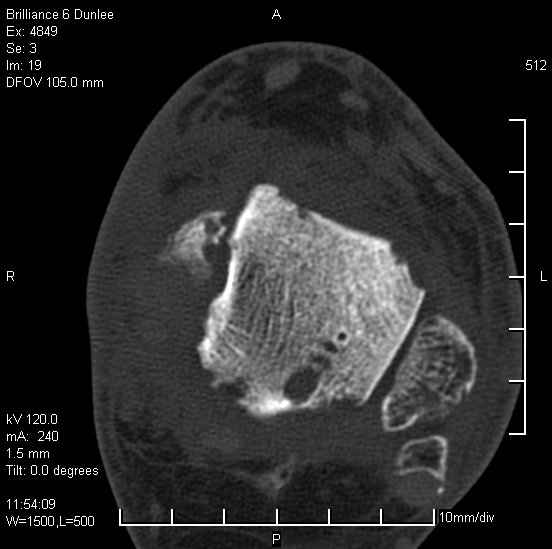

На лечении находится пациент 35 лет. Травма в сентябре 2008 г.- открытый вывих таранной кости

В день травмы ПХО, вправление вывиха, трансартикулярная фиксация. Рана зажила первично. С января нагрузка на конечность. С конца апреля- болевой синдром. На рентгенограммах и КТ признаки ас. некроза таранной кости, артроз подтаранного и голеностопного суставов.